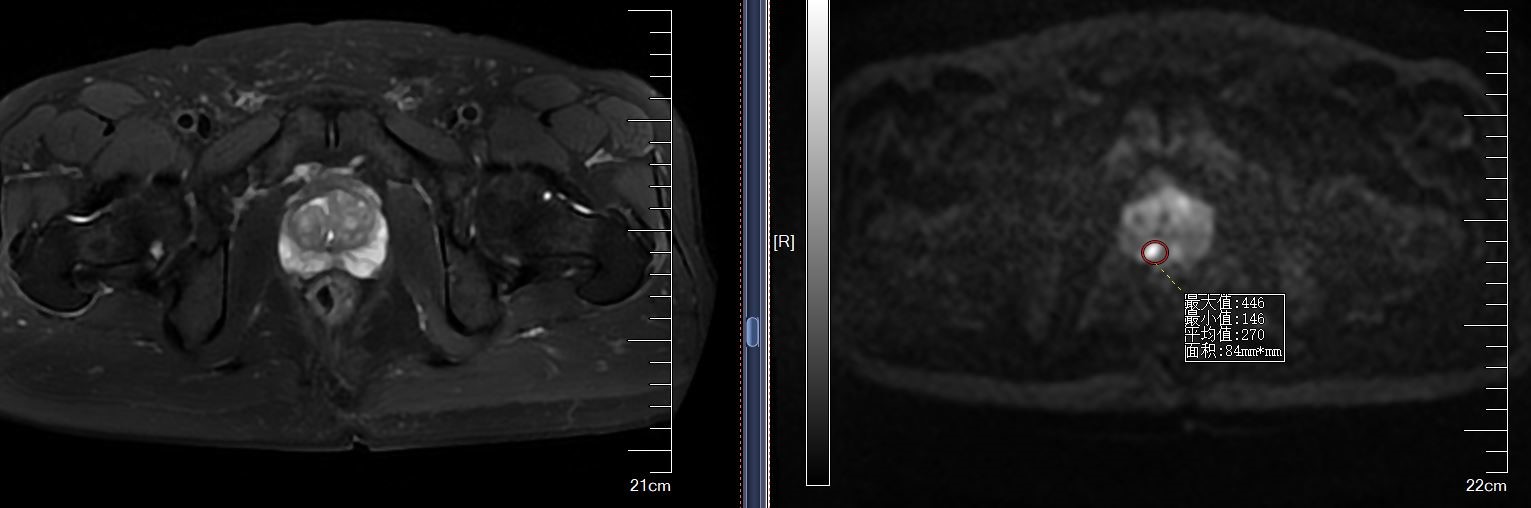

mpMR-TURS融合穿刺(RVS)是指将患者已出结果的核磁(MRI图像)与经直肠超声图像(TURS)融合,在超声实时引导下,对核磁可疑靶点进行精准导航穿刺,将CT/MRI的高度敏感性与超声的实时性联合应用。

我院已成功开展病例,患者张大爷因“体检发现PSA升高一周”入院,前列腺特异性抗原升高,入院后完善磁共振提示前列腺右侧外周带异常信号影,行多影像融合介入导航术。

穿刺过程

术前拷贝该患者核磁数据并导入机器中,经过核磁病灶定位,超声图像显示,匹配对位后,实施前列腺穿刺术,手术共用时12分钟,共穿刺14针,常规穿刺12针,核磁可疑病灶区追加2针。